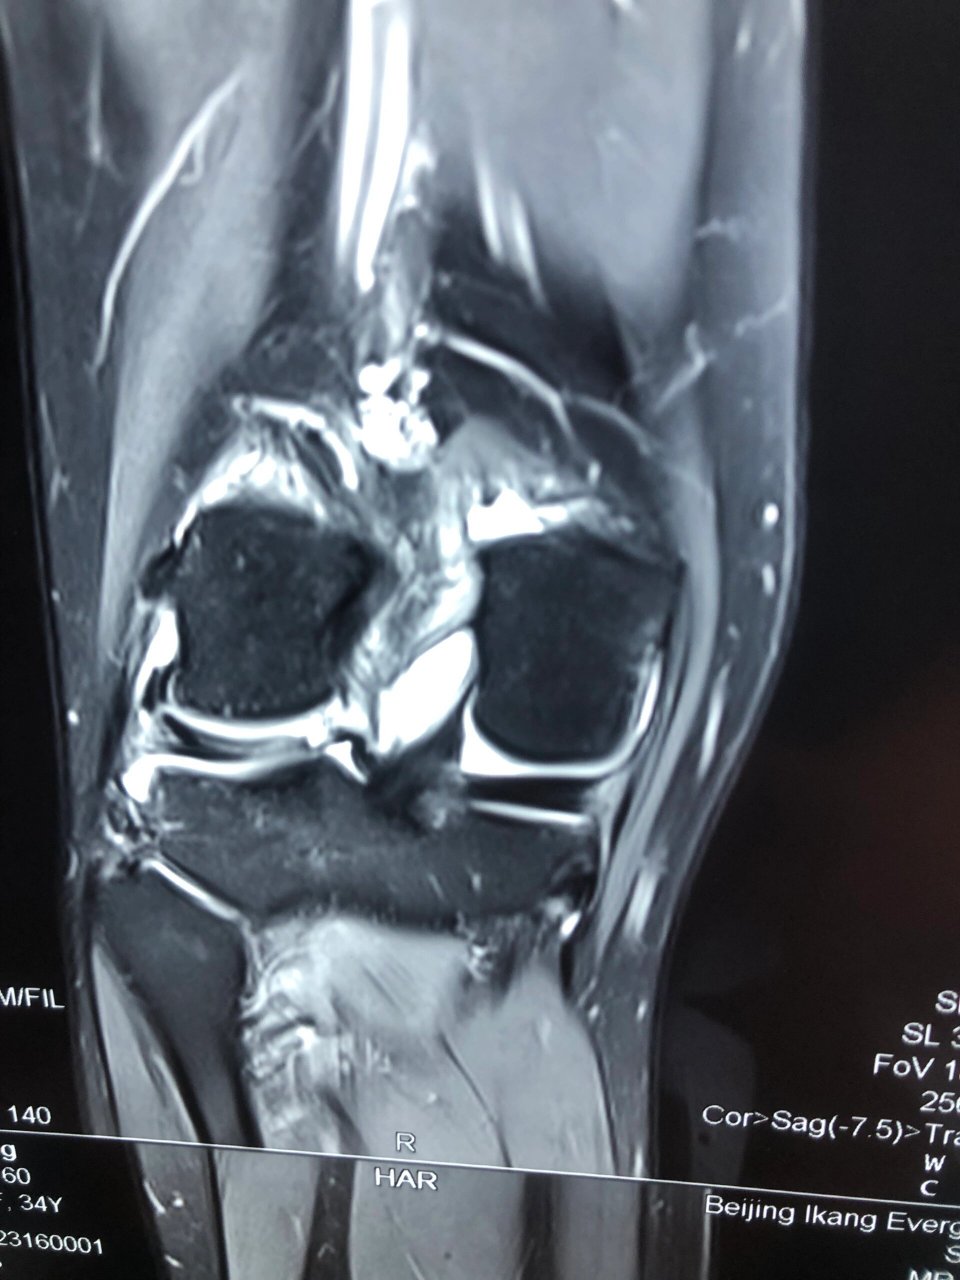

外侧盘状半月板损伤核磁表现 今天两台手术之一,外侧盘状半月板损伤

图片尺寸960x1280